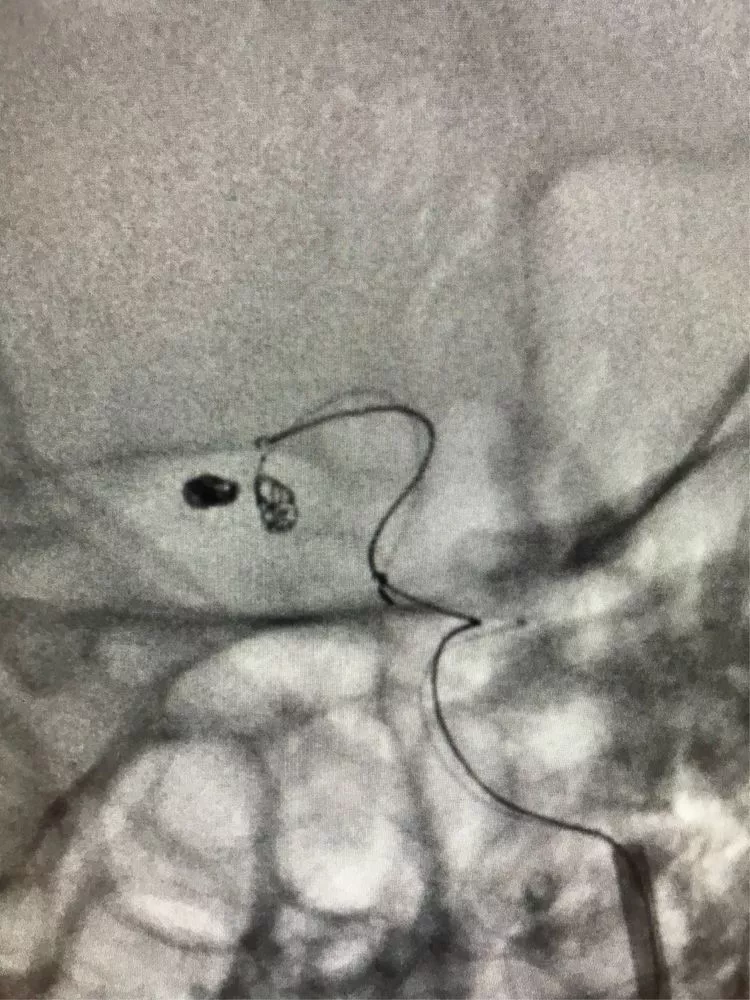

2根微导管进入2个子瘤,1号子瘤内弹簧圈能稳定填入,2号子瘤内弹簧圈不能稳定填入。

先把1号子瘤填瓷实。

再把1号微导管退到主瘤内,部分填入弹簧圈挡住2号子瘤的开口。